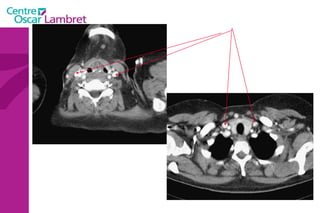

Les  artères Carotides Communes  : La droite vient du TABC. La gauche vient de la crosse de l’aorte. Elles n’ont aucune branche collatérale. L’appareil circulatoire

Les artèresCarotides Communes : La droite vient du TABC. La gauche vient de la crosse de l’aorte. Elles n’ont aucune branche collatérale. L’appareil circulatoire

L’artère carotide primitive droite : Elle naît à 3 cm en arrière de l'articulation sterno-claviculaire à la hauteur de T1. monte dans la gouttière carotidienne le long de la trachée et du corps thyroïdien, de l'oesophage puis du larynx et du pharynx.  Elle s’évase avant sa terminaison en regard du bord supérieur du cartilage thyroïde et de C4.  L’appareil circulatoire

L’artère carotide primitivedroite : Elle naît à 3 cm en arrière de l'articulation sterno-claviculaire à la hauteur de T1. monte dans la gouttière carotidienne le long de la trachée et du corps thyroïdien, de l'oesophage puis du larynx et du pharynx. Elle s’évase avant sa terminaison en regard du bord supérieur du cartilage thyroïde et de C4. L’appareil circulatoire

L’artère carotide primitive gauche  : naît directement de la crosse aortique et comporte un premier segment intra thoracique en arrière du manubrium sternal. Son segment cervical est identique à celui de la carotide primitive droite.  L’appareil circulatoire

L’artère carotide primitivegauche : naît directement de la crosse aortique et comporte un premier segment intra thoracique en arrière du manubrium sternal. Son segment cervical est identique à celui de la carotide primitive droite. L’appareil circulatoire